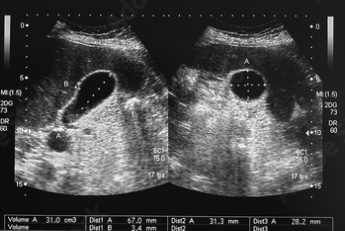

Ecografía abdominal: Es la técnica de imagen más utilizada y efectiva para detectar cálculos biliares y observar la inflamación en la vesícula.

Ecografía Abdominal para detectar cálculos biliares y evaluar la inflamación.